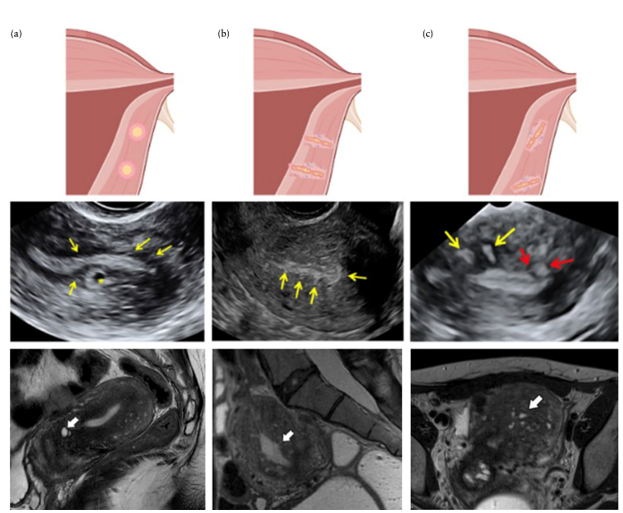

Việc các thay đổi về mặt mô học của JZ được nhận biết là Adenomyosis trên TVS hay MRI hay không còn phụ thuộc vào định nghĩa được sử dụng và tiêu chuẩn chẩn đoán. Cuối cùng, chẩn đoán Adenomyosis được xác định bằng sự hiện diện của các tuyến nội mạc tử cung lạc chỗ trong cơ tử cung hoặc xâm nhập vào JZ. Các thay đổi này có thể thấy được trên cả TVS và MRI (Hình 3).

Hình 3: Các dấu hiệu trực tiếp của Adenomyosis. Cột (a): các nang cơ tử cung; Cột (b): các đường và nhú (lines and buds) dưới nội mạc tử cung phá vỡ JZ; Cột (c): các đảo tăng âm trong cơ tử cung. Hàng trên cùng trình bày sơ đồ tử cung ở mặt phẳng coronal, hàng giữa trình bày trên mặt phẳng đứng dọc bằng hình ảnh trên TVS, hàng dưới cùng trình bày trên mặt phẳng đứng dọc bằng hình ảnh MRI chuỗi xung T2.